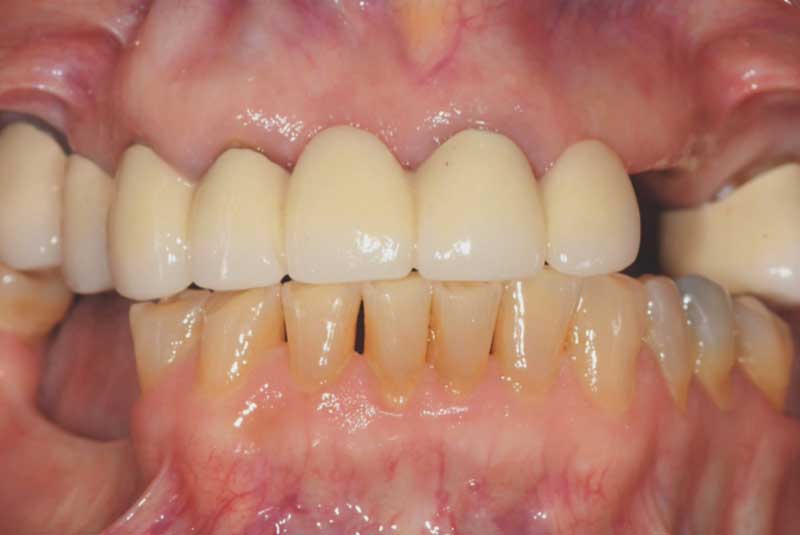

The patient had her implants placed 20 years ago. Four implants, particularly in the maxilla, were not positioned ideally for me to utilize and restore, while the four implants in the mandible were outdated and no longer functional. The patient's primary concern is to restore both function and aesthetics.

All on 6: Facial cut back (PFZ) Zirconia Full arch prosthesis for Maxilla and Mandible Before & After